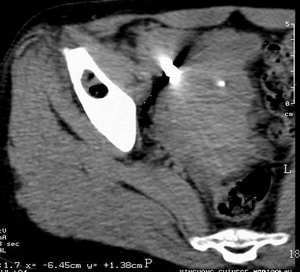

需要明确的一个问题是病变内部的低密度影究竟是脂肪密度还是气体密度,有时如果不用宽窗观察,二者是很难区分的,如果是气体密度的话,这将有是继天天红发布的2085以后又一例邻关节骨囊肿,该病完全可以和关节不相通。下面的图片是天天红的病例,请大家和本例比较一下:。

希望guo6607能够提供低密度影的ct值